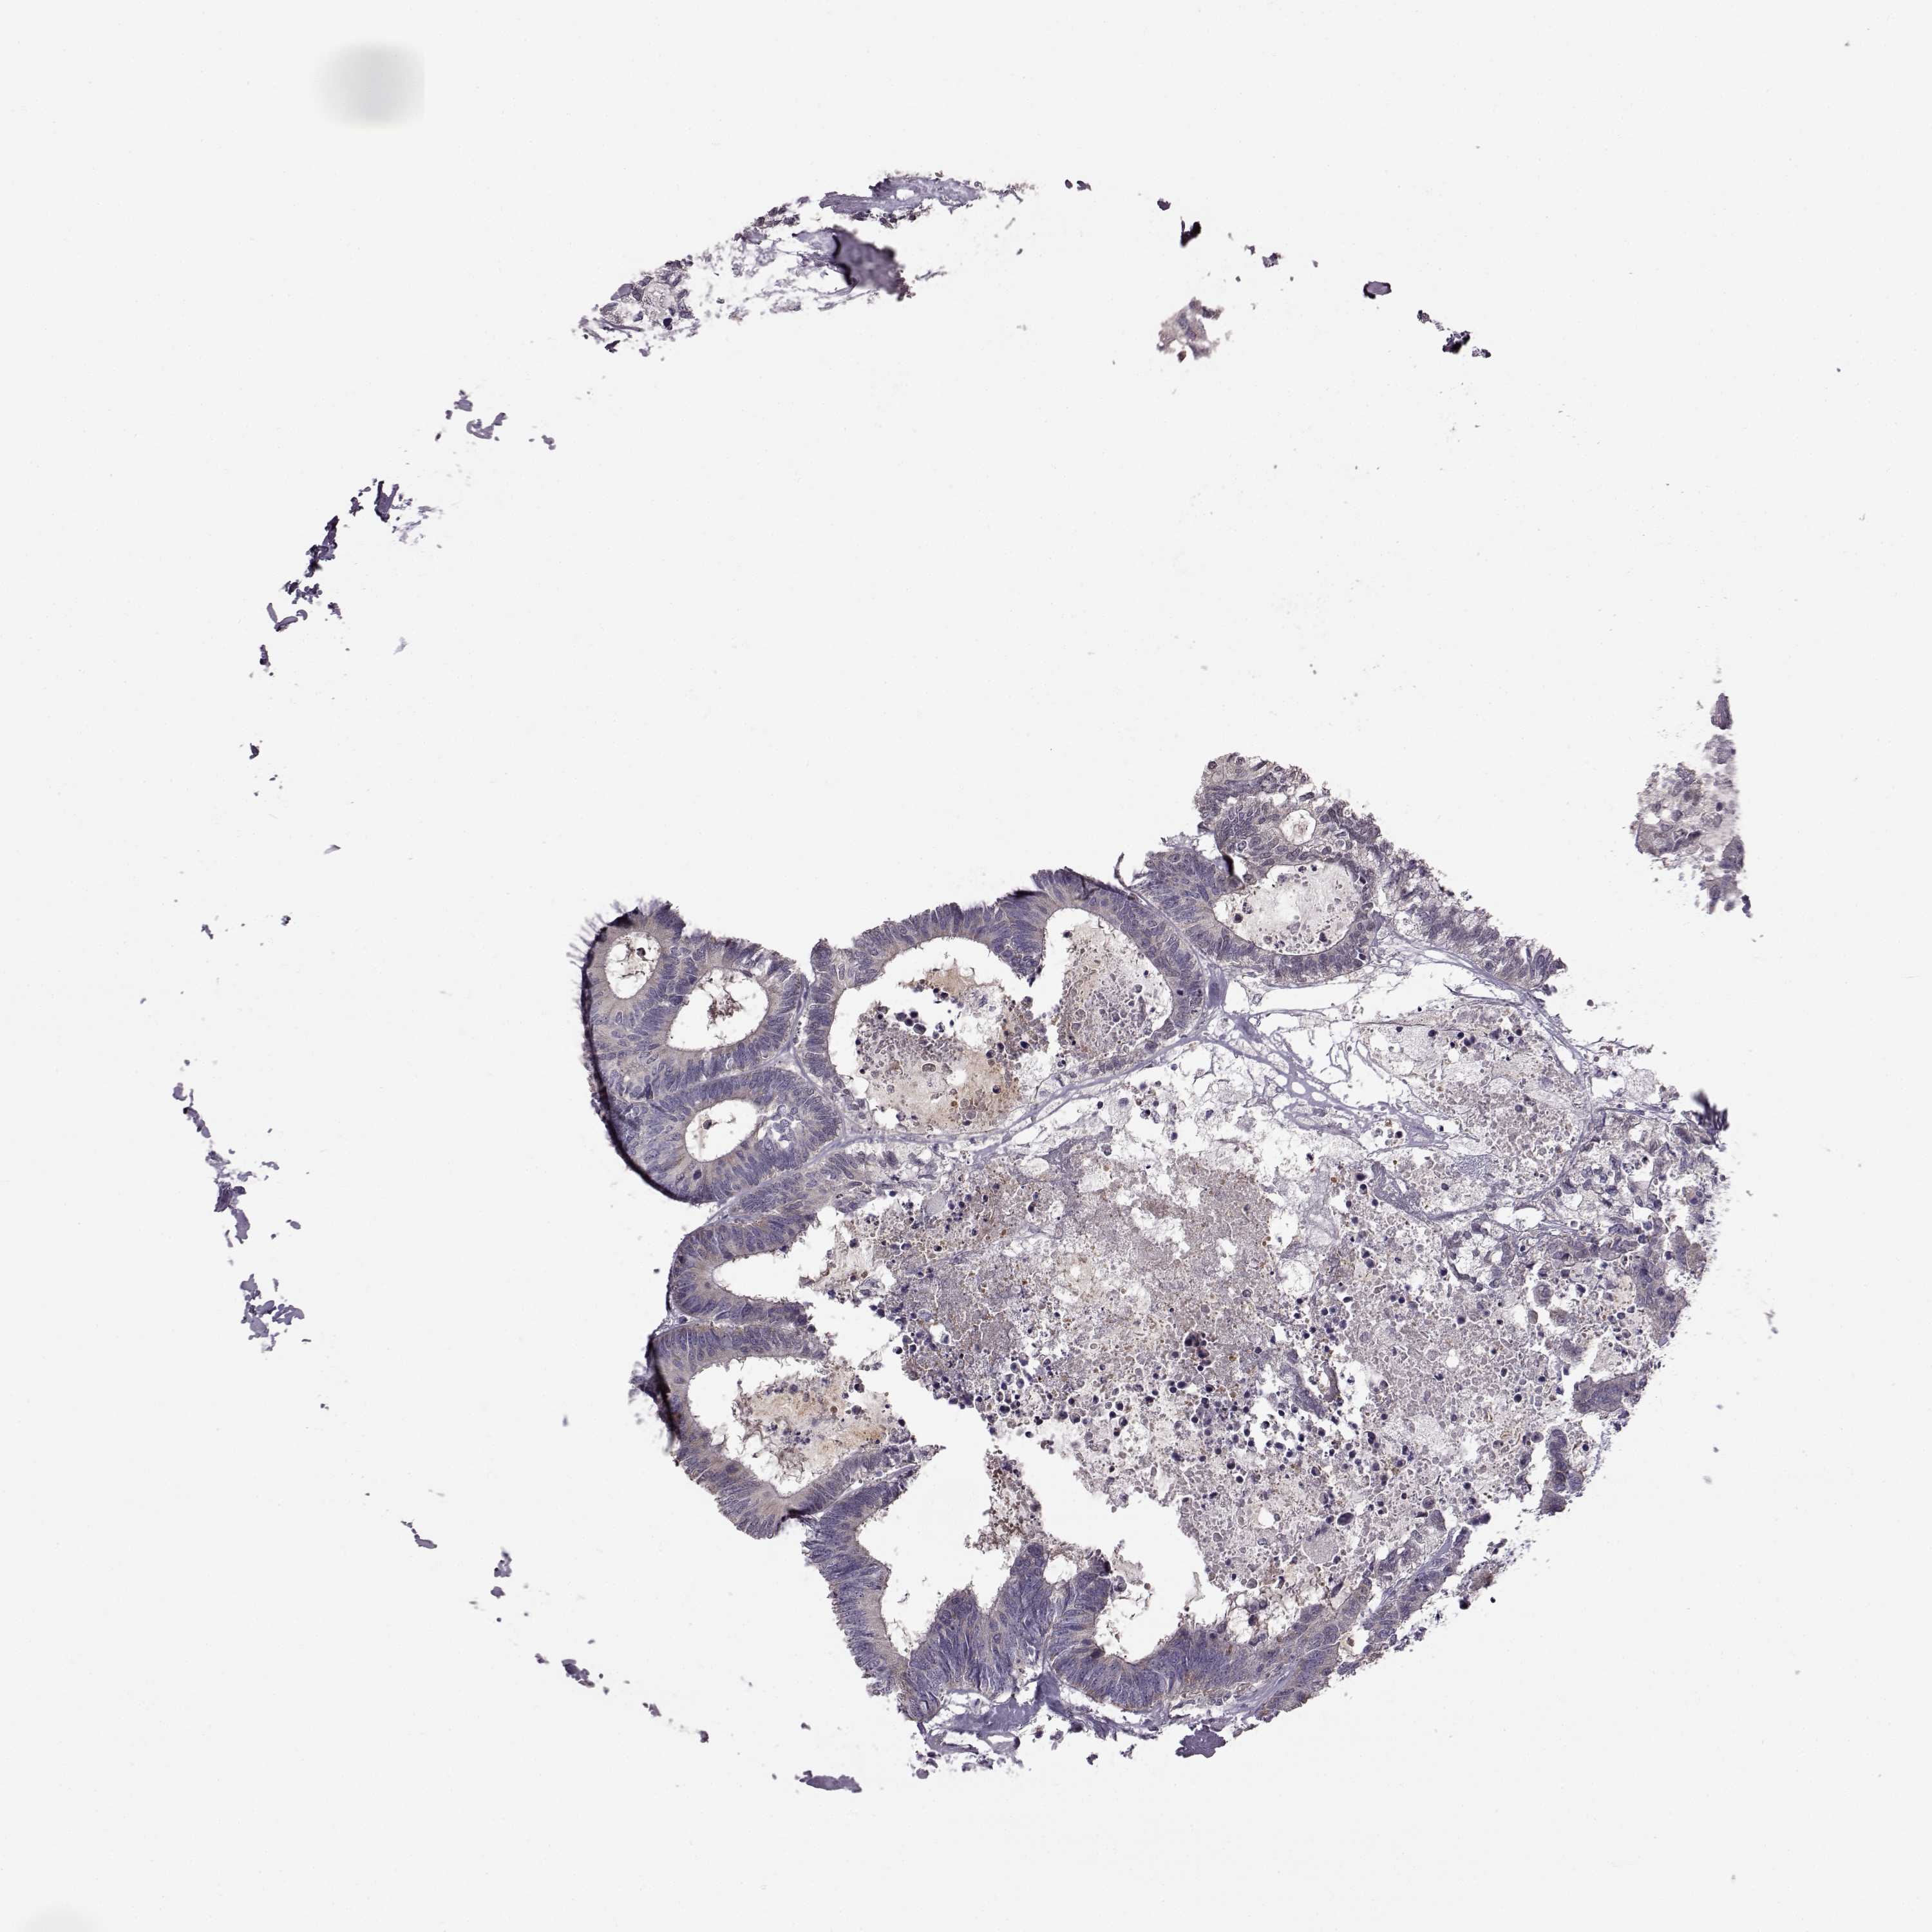

CANCER COLORECTAL CANCER Show tissue menu

COAD TCGA COAD VALIDATION READ TCGA READ VALIDATION PROTEIN COAD CPTAC PROTEIN EXPRESSION

Colorectal cancer

Rectum adenocarcinoma